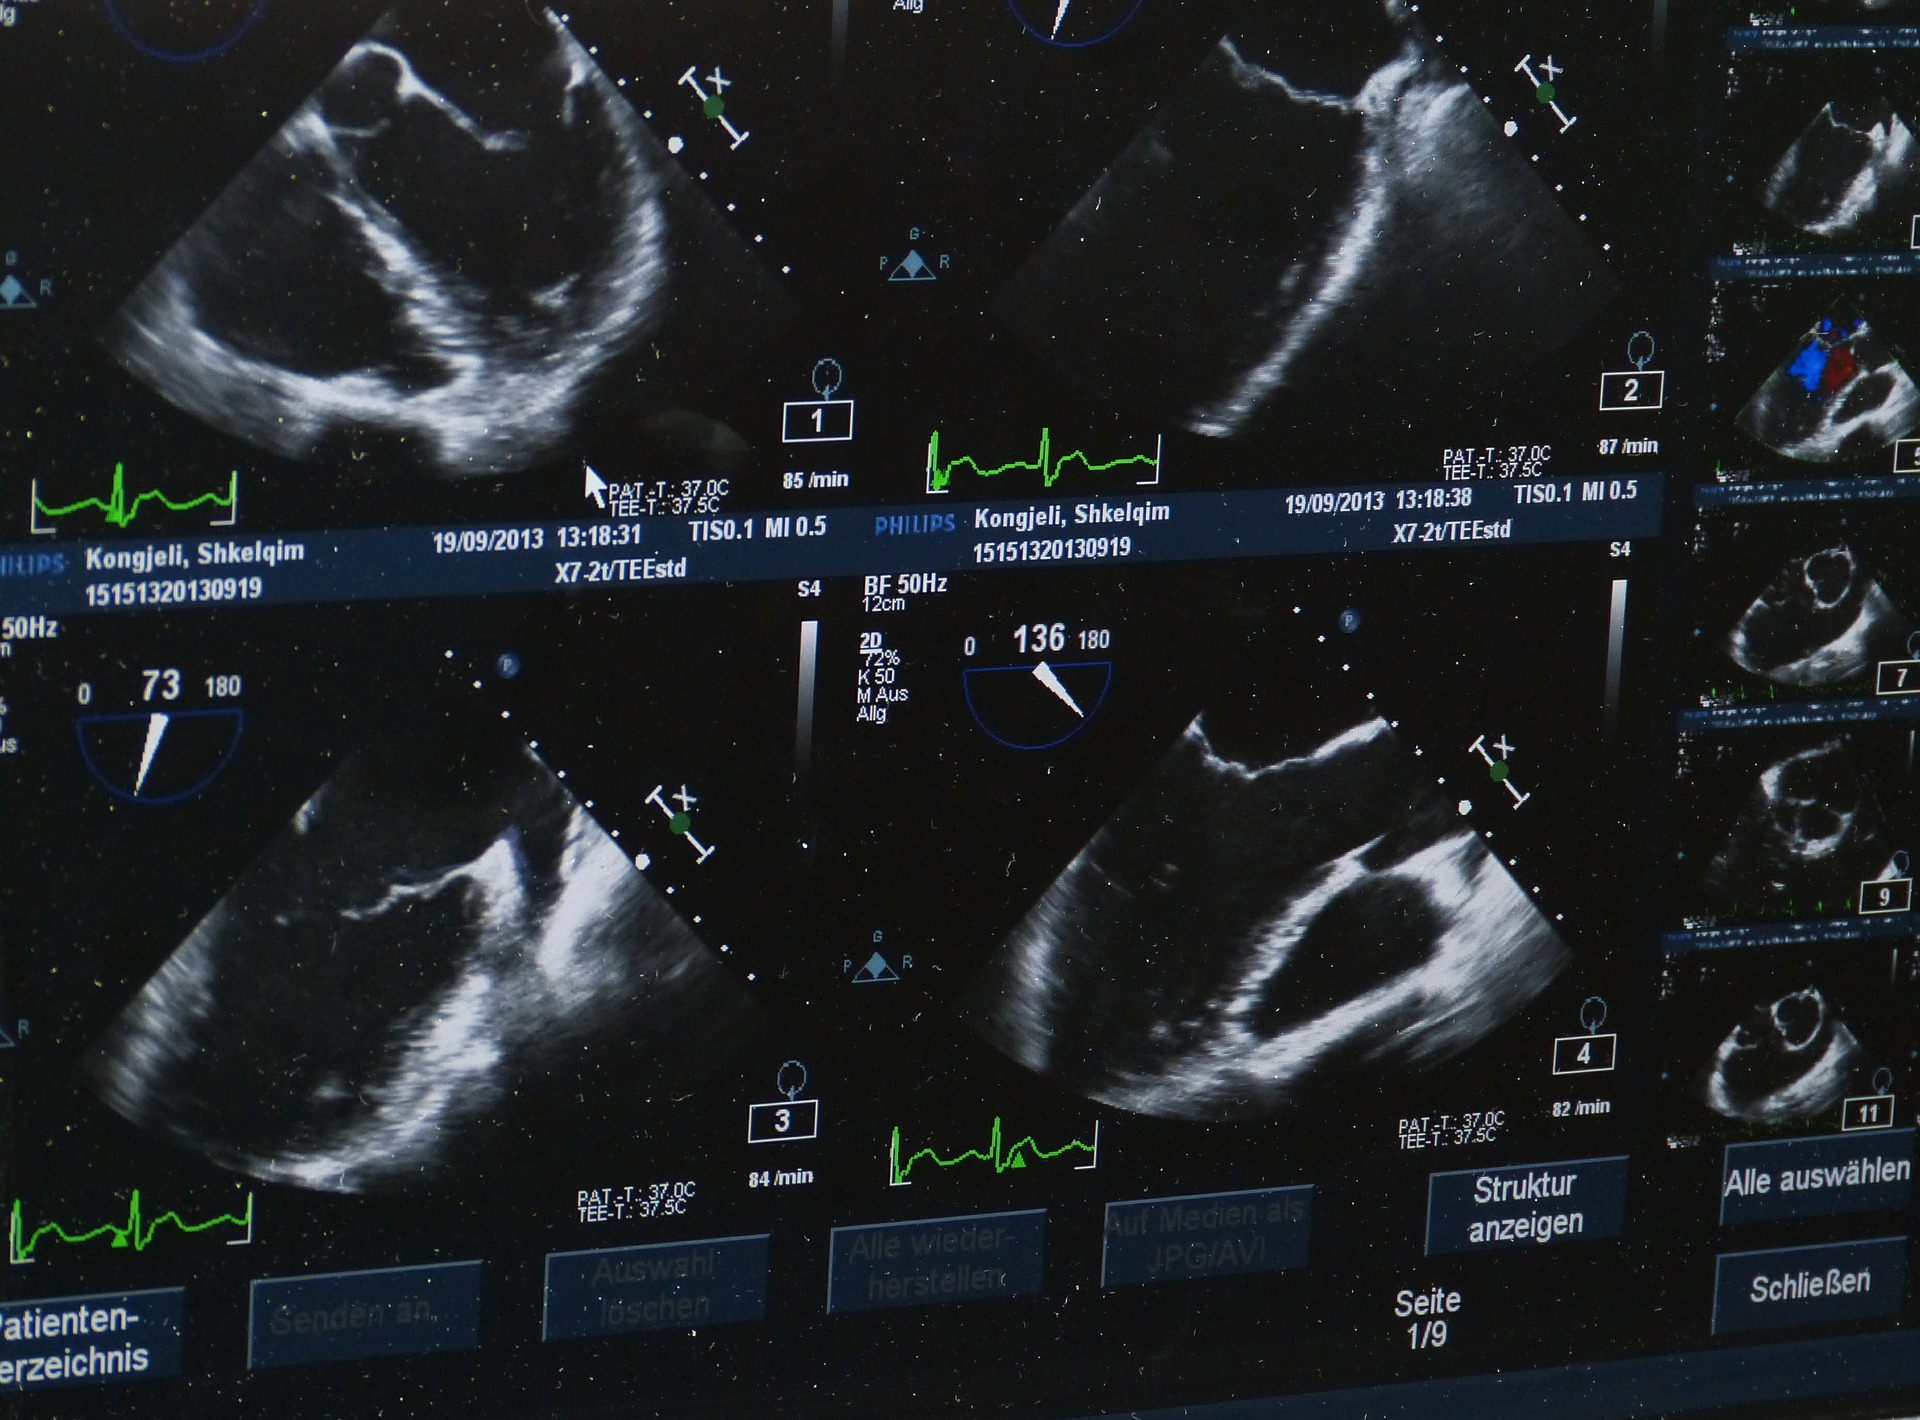

➤ Adult Echocardiography (AE)

Evaluate valve function, chamber size, wall motion, and ejection fraction. You'll use M-mode, 2D, spectral and color Doppler.

Sonographers love adult echo for its clinical depth and direct impact—your work helps guide diagnoses like heart failure, valvular disease, and cardiomyopathies.